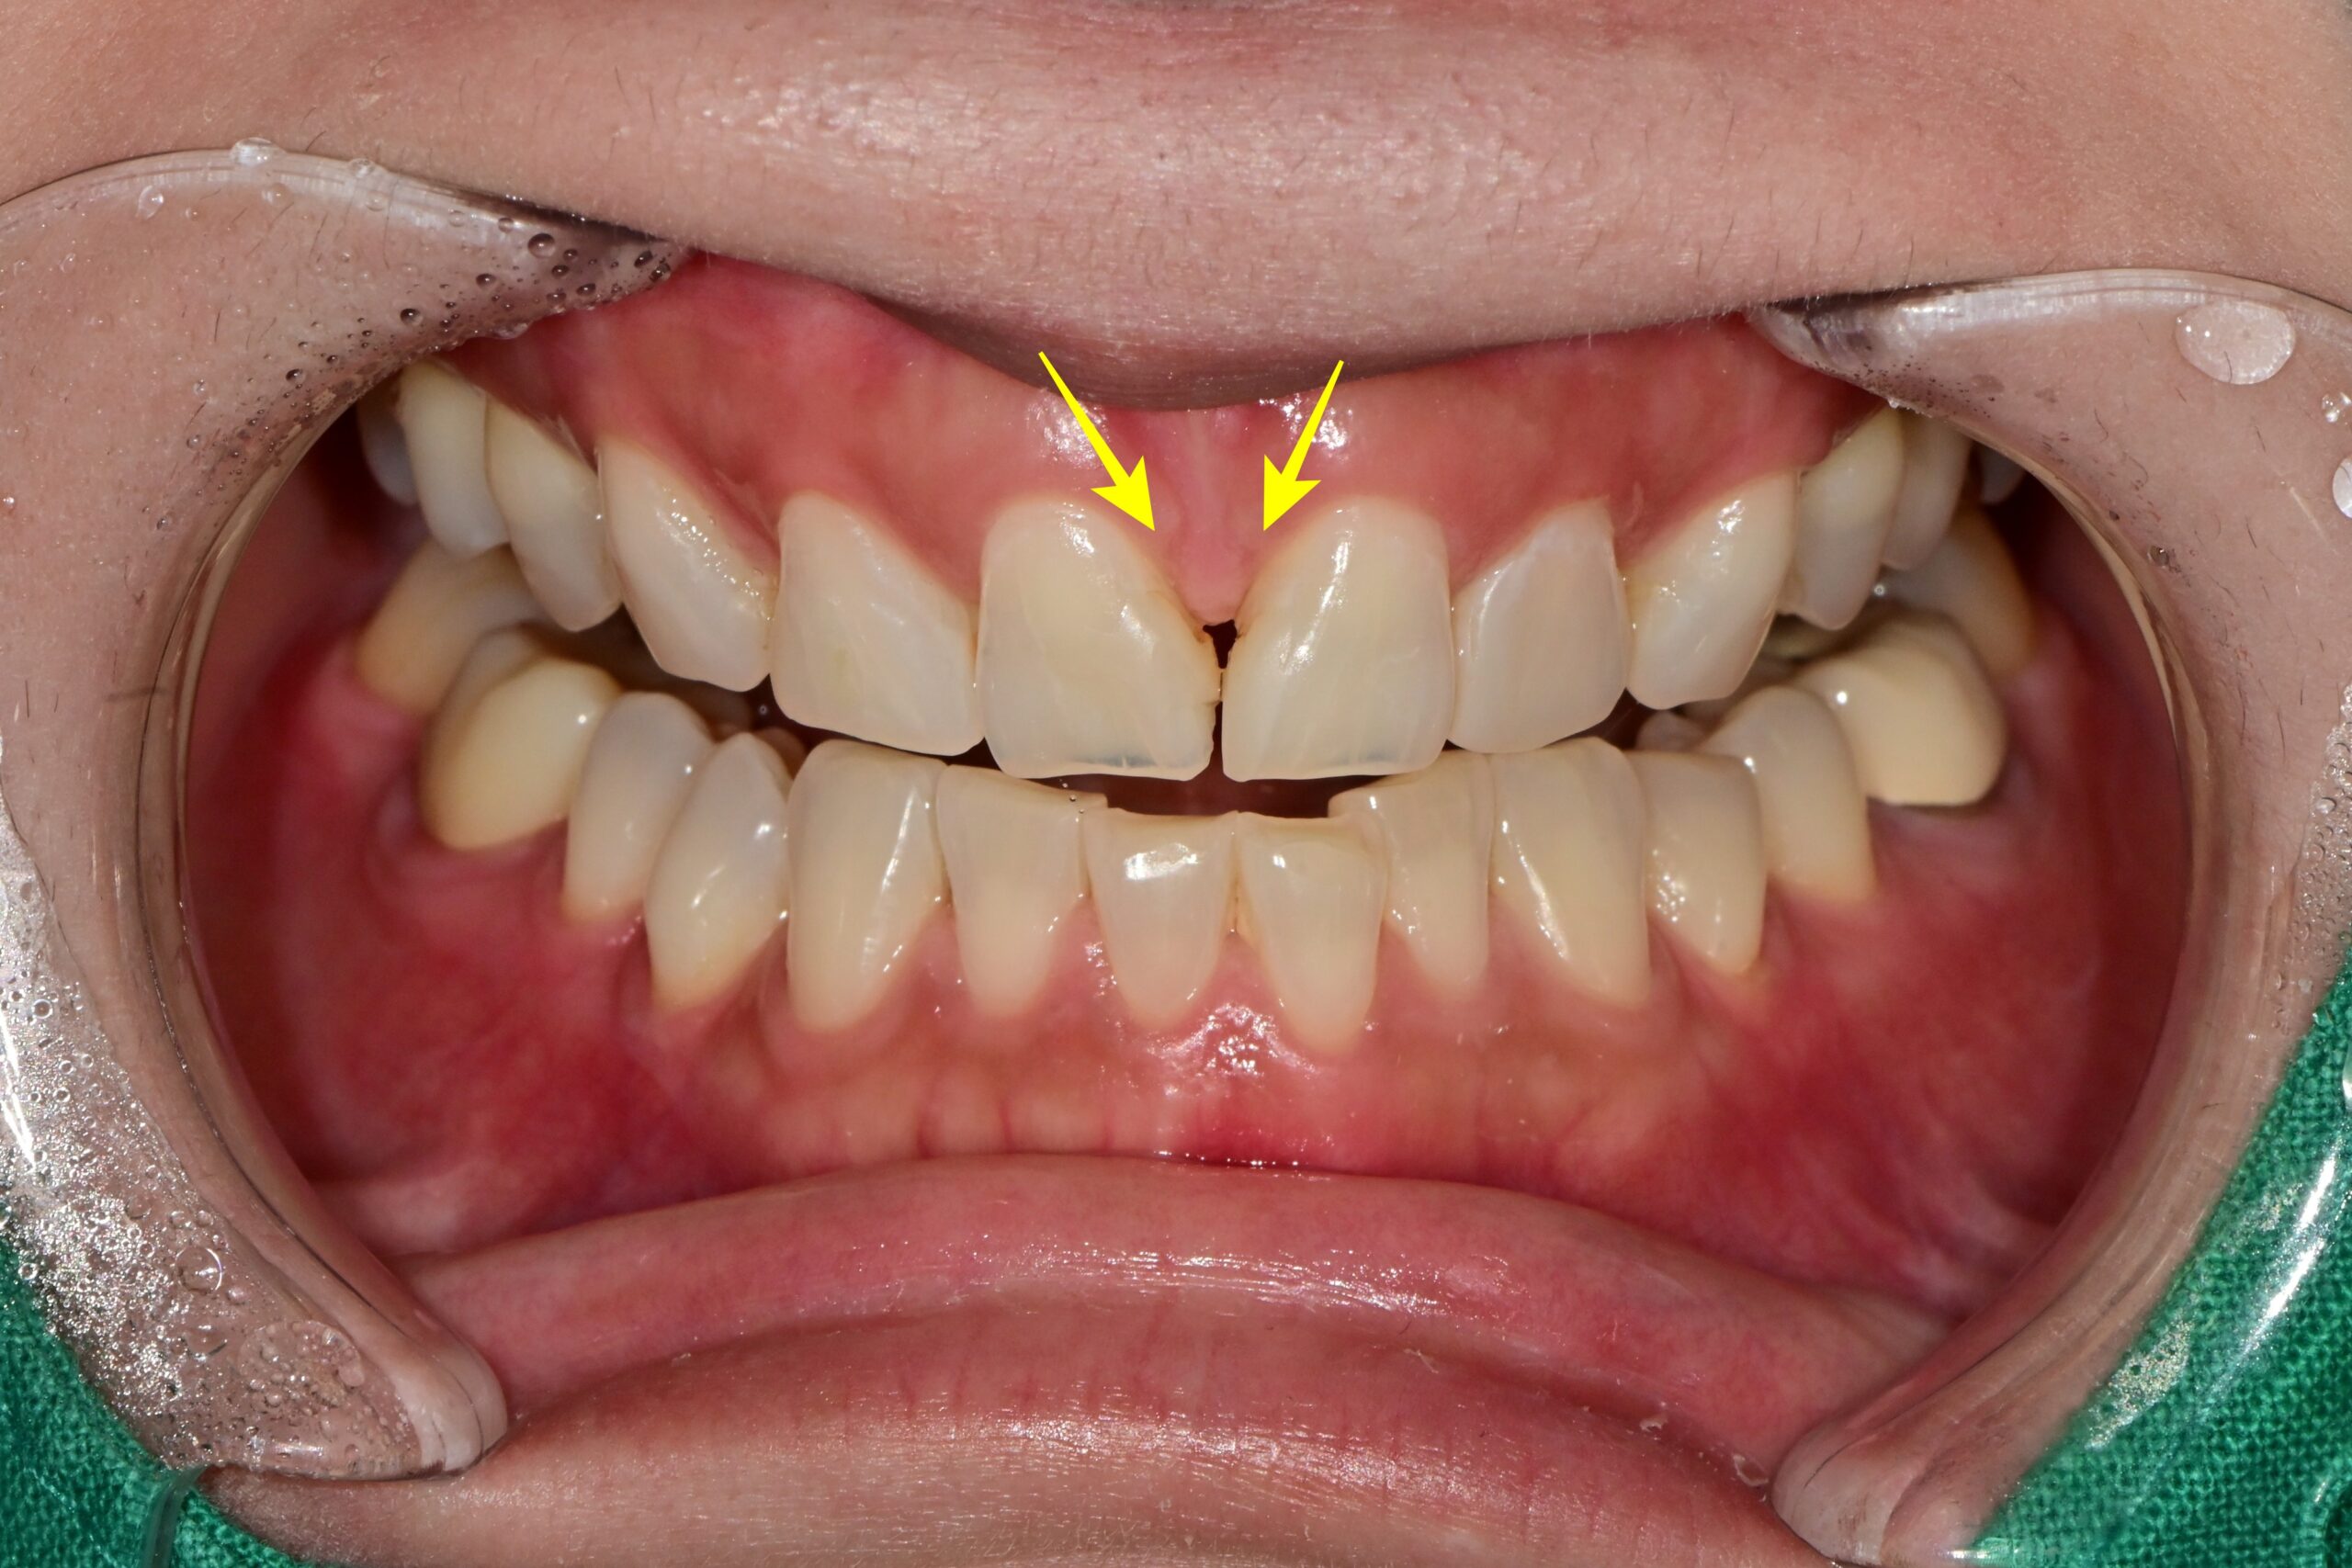

상하악 전치부 하얀 반점 4곳 화살표 치료 전